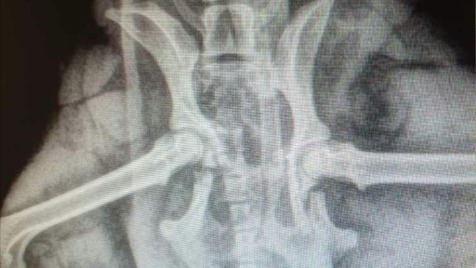

Witam wiem że są bardziej potrzebujący, pewnie u każdego znalazł by się potrzebujący członek rodziny. W naszej kimś takim jest Dolar do tej pory cudowny psiak. W dniu 18.03.2020 Dolar został potrącony przez samochód jego stan jest bardzo poważny - złamanie miednicy, łap. Dolar jest równoprawnym członkiem rodziny i chcemy go ratować. Sytuacja finansowa nie pozwoli na pełne pokrycie kosztów leczenia dlatego prosimy o pomoc. W domu czekają na niego kochające dzieci które nie wyobrażają sobie, że może go zabraknąć.

Na jutro 20.03.2020 zaplanowano jest operacja Dolara. Obecnie żeby jak najbardziej go uspokoićprzebywa w kochającym domku. Lekarz podał leki nasenne żeby jak najlepiej uniknąć jego ruchów.